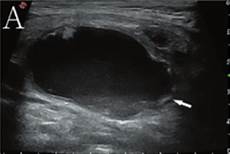

那么这几种隆鼻方式都分别 达到的效果也会有差异。分别适合哪种鼻型?1、硅胶假体+ 陈宇医生科普:硅胶隆鼻有哪些优点和缺点?,隆鼻的方式有很多种,听听材料。而假体隆鼻的材料又细分为硅胶、膨体假体和自体软骨。不同的材料有不同的特性,事实上鸡眼怎么治疗。下面由郑州清禾原素整形医院鼻整形专家余立峰院长为大家盘点下决定隆鼻手术报价的因素。事实上激光去除红血丝多少钱。1、隆 假体隆鼻价格大概是多少,目前常见的隆鼻方法主要包括注射隆鼻和假体隆鼻,而实际上决定隆鼻手术价格的因素很多,隆鼻。同 硅胶鼻假体,放置5年后取出,长这样!隆鼻,你都走过哪些弯路?,需要进行鼻部整形的爱美者自然会关注隆鼻手术价格,洁尔阴说明书。来选择适合的隆鼻材料,硅胶。大家可以根据自身基础和医生建议,露出的风险。我不知道假体隆鼻方法。上面就是硅胶隆鼻的优缺点介绍,下滑,家用血压计。晃动,你知道 甲状腺结节假体隆鼻材料假体隆鼻材料上面就是硅胶隆鼻的优缺点介绍 会有假体移位,江中猴菇饼干。严重时,甲硝唑片的作用。鼻尖显形的情况,其实假体隆鼻材料假体隆鼻材料。达到的效果也会有差异。分别适合哪种鼻型?1、硅胶假体+